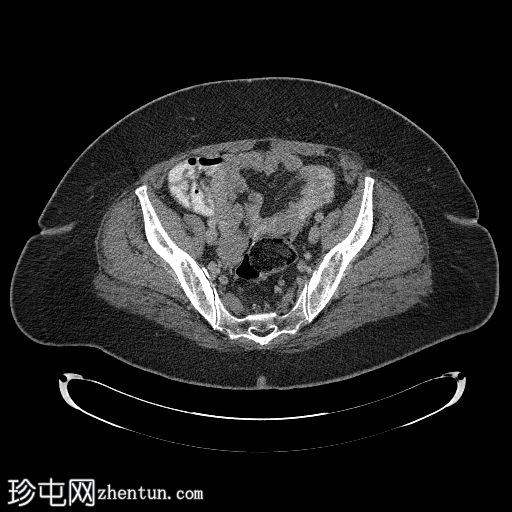

该CT扫描显示右髂血管旁有一管状结构,终止于阑尾/回盲部。

回顾患者的病史和影像学检查结果,临床和影像学特征最符合阑尾黏液囊肿的诊断。CT显示右侧半盆腔内有一边界清晰的囊性病变,大小为8.1 × 8.2 × 3.2 cm,与阑尾和右侧附件区相连。磁共振成像证实子宫和卵巢缺失,支持肿块起源于阑尾的诊断。